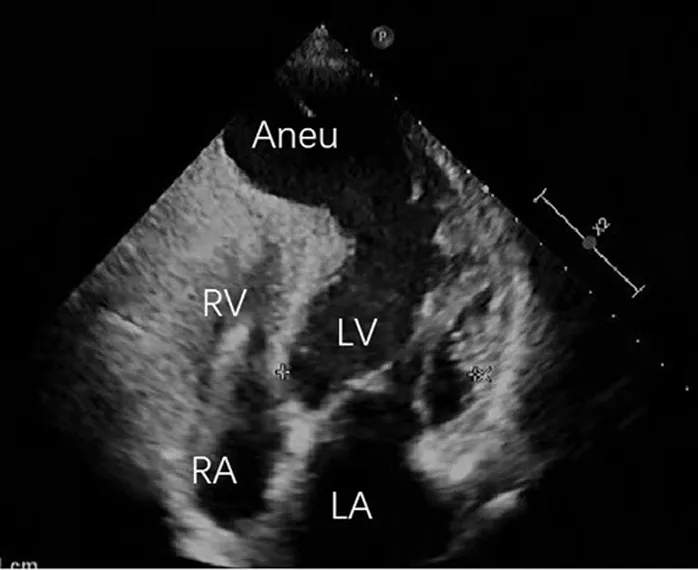

针对心尖部室壁瘤的典型症状,鉴别诊断需重点排除以下常见病因:1)肥厚型梗阻性心肌病:经胸超声心动图显示巨大解剖性心尖前壁室壁瘤,约占左心室容积60%,伴收缩期反常运动,根据该表现排除肥厚型梗阻性心肌病诊断(图1、2);2)冠状动脉疾病:冠脉造影提示未见明显狭窄、心肌桥或血流异常,据此排除冠状动脉相关疾病(图2)。

图1 术前经胸腔超声心动图

图注:Aneu=室壁瘤;LA=左心房;LV=左心室;RA=右心房;RV=右心室;TTE=经胸超声心动图

经胸超声心动图提示:巨大解剖性心尖部室壁瘤,约占左心室容积60%,伴收缩期反常运动(图1);室间隔呈代偿性肥厚,而左心室中段及基底段收缩正常。负荷成像提示:重度人工瓣膜狭窄(峰值流速4.4 m/s,峰值与平均跨瓣压差分别为74 mmHg与41 mmHg),中度二尖瓣反流,左心室射血分数减低(25%)。CTA提示:前壁心尖部存在巨大室壁瘤(图3A、3B);左心室舒张末期容积为184 mL,收缩末期容积为119 mL,射血分数为38%(图3C)。动态心电图监测显示:窦性心律与起搏心律并存,多形性室性早搏,完全性右束支传导阻滞,以及短阵室性心动过速;心室异位激动灶可能起源于前乳头肌根部。